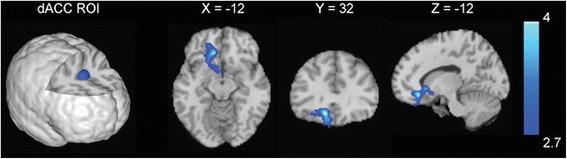

Compared with LPs, FPs showed decreased rsFC between the dorsal anterior cingulate cortex (dACC) and the subgenual anterior cingulate cortex, medial orbitofrontal cortex (mOFC), and ventral striatum. Among FPs, rsFC strength between the dACC and the bilateral dorsolateral prefrontal cortex (DLPFC), the bilateral dorsal striatum, and the left temporal gyrus was inversely correlated with attentional bias to smoking cues.